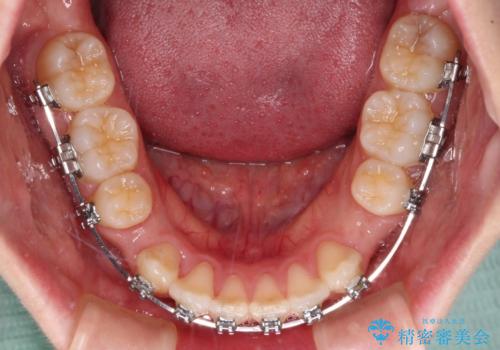

- メタルブラケット

- 1年9ヶ月

上下ともに歯列が前方に突出していたため、上下左右の第一小臼歯4本を抜去し、ワイヤー装置による矯正治療を行うこととしました。

上下左右4本抜歯する場合には、通常2年から2年半ほどの期間を要しますが、舌のトレーニングをしっかりと行っていただいたことで、1年9ヶ月で終了することができました。